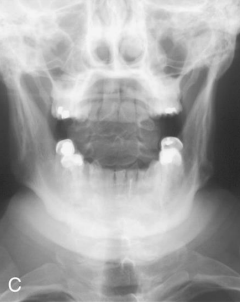

AP Open Mouth: Is this Image Good?

No.

Front incisors are superimposed over C1-C2

Atlantoaxial joint is not demoed

Excessive flexion of skull and neck

Reposition with slight extension of the neck or angle the CR slightly cephalic